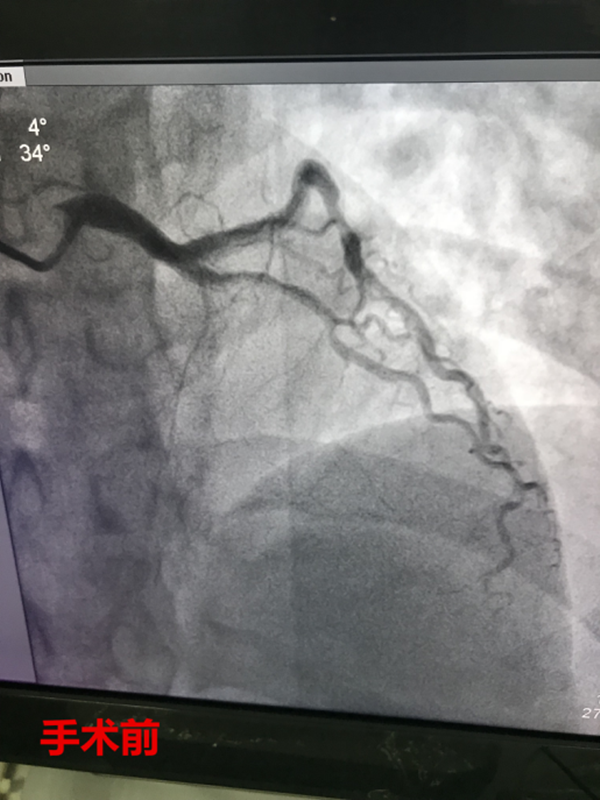

11時12分,路艷主治醫(yī)師護送患者繞行急診科及CCU,直達介入室。徐曉輝主任、耿蓬勃、師軍峰副主任醫(yī)師以及介入室護士郭紀文、于永利、霍貝貝等人員立即就位,手術(shù)開始,穿刺、造影、導絲通過、球囊擴張、支架植入,為患者實施的急診手術(shù)一切都緊張有序的進行……11時45分,手術(shù)順利完成,DtoB時間(患者進入醫(yī)院大門至PCI介入手術(shù)球囊擴張的時間)僅僅26分鐘,遠遠超出了國家對胸痛患者DtoB的時間要求(國家胸痛中心DtoB時間要求<90分鐘)。